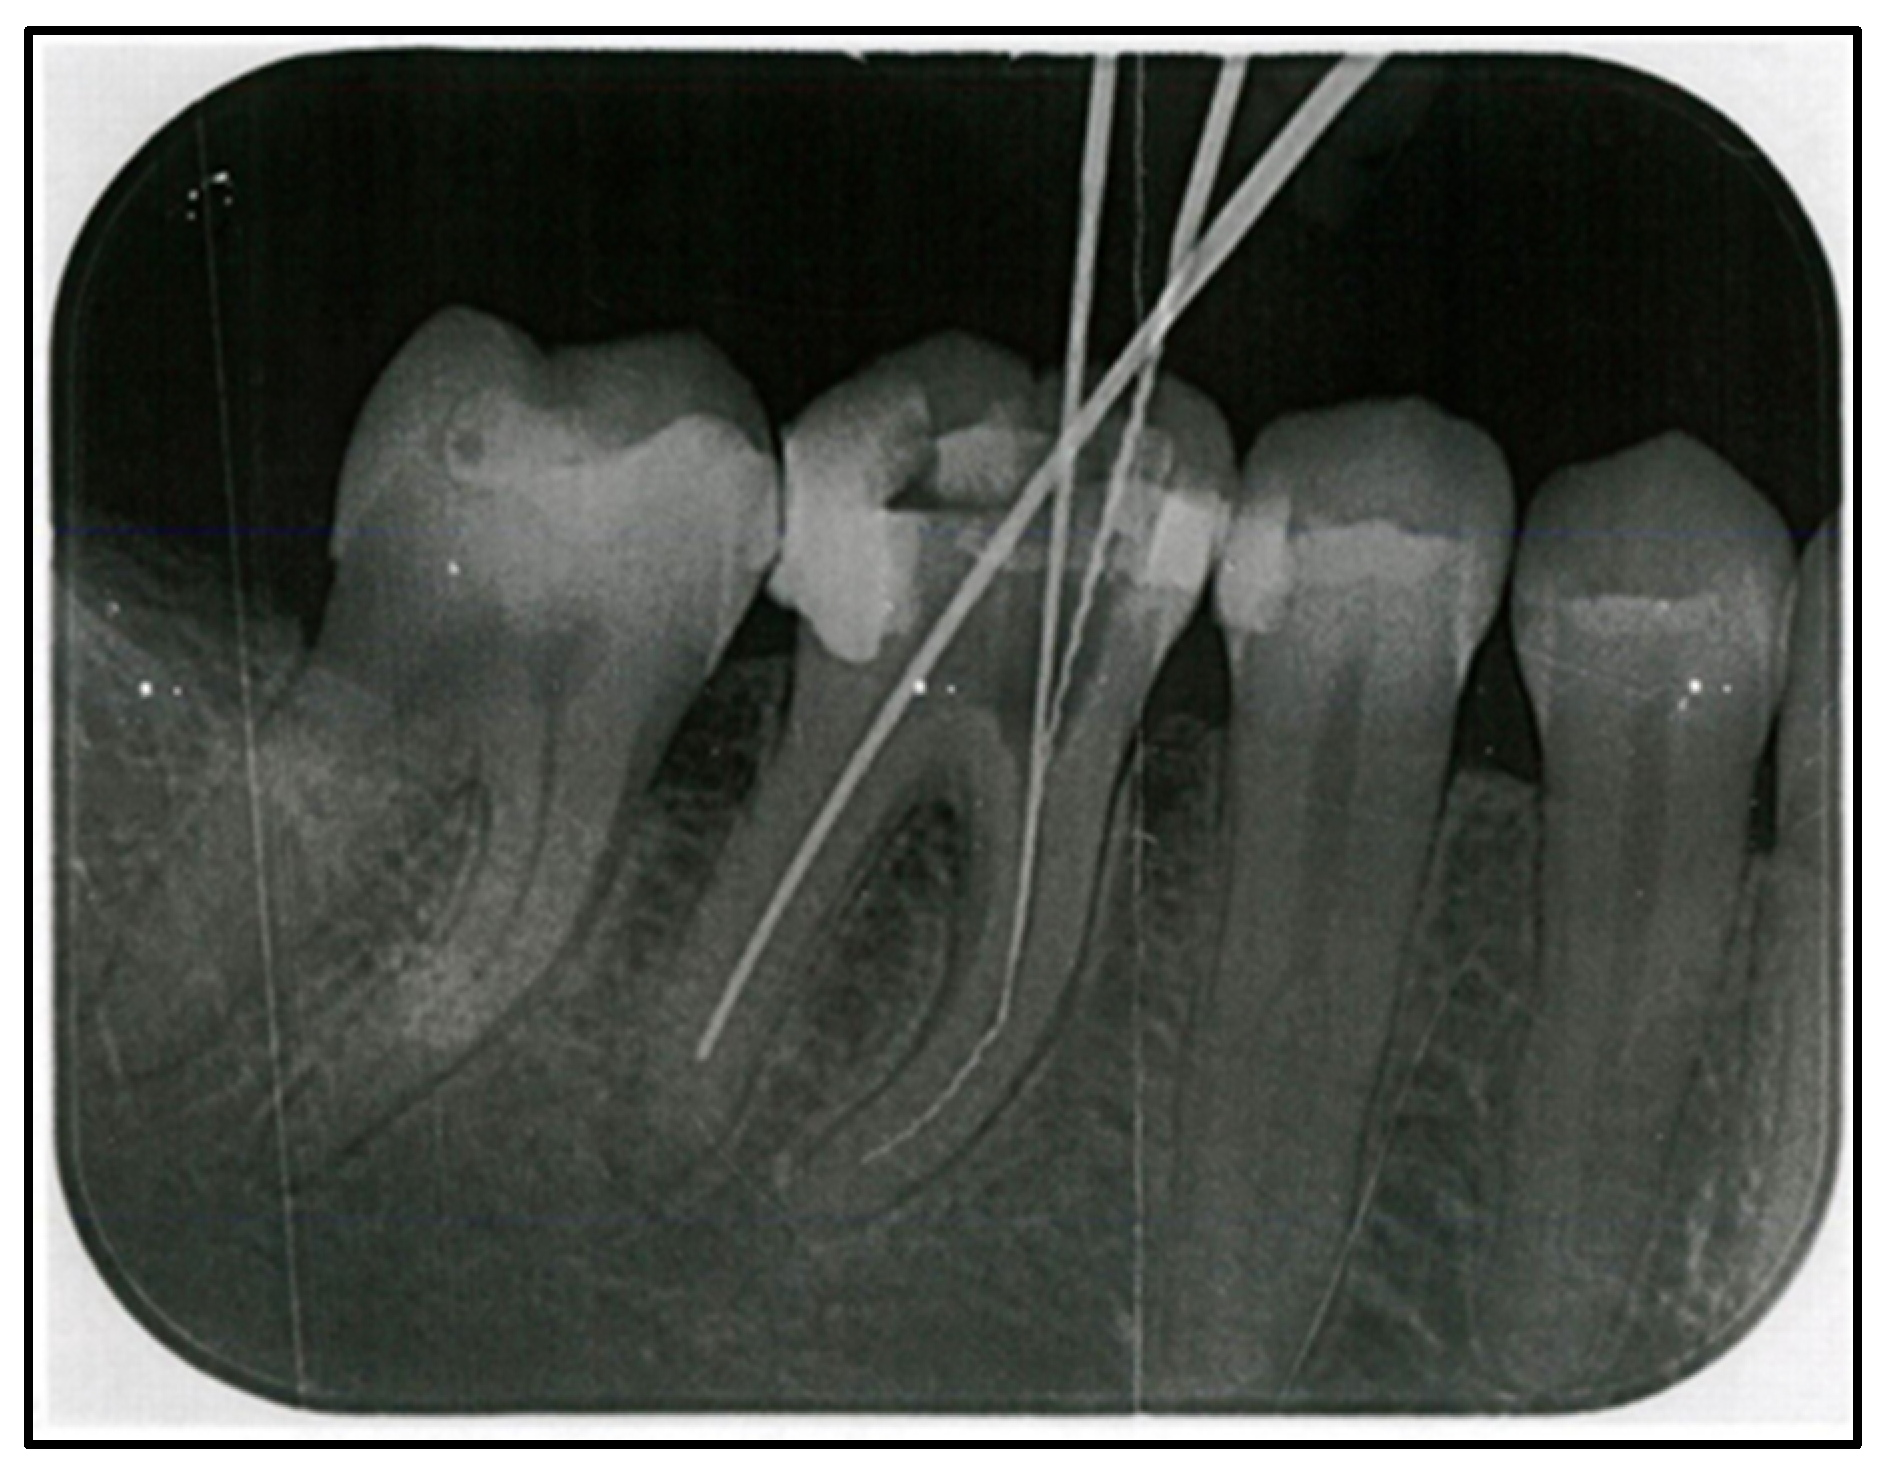

2. Case Report